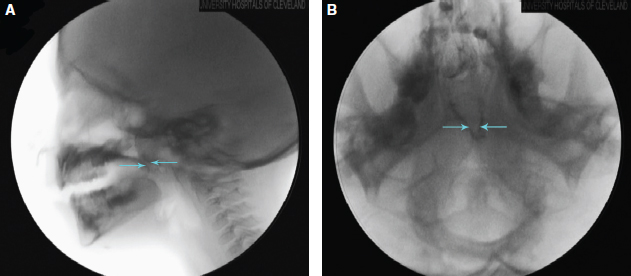

48 ○ The classic diagnostic triad of overt submucous cleft palate includes a bifid uvula, notched hard palate, and zona pellucida. ○ The prevalence of submucous cleft palate ranges from 0.02% to 0.08% in the general population, although it is significantly higher in patients who have velopharyngeal inadequacy (VPI). ○ Occult submucous cleft palate is diagnosed by multiview videofluoroscopy and nasal endoscopy during workup for VPI. ○ A specific familial cause of submucous cleft has not been identified, although it is commonly associated with other comorbid craniofacial differences, either sporadic or as part of a syndrome such as velocardiofacial (22q11 microdeletion), Klippel-Feil, or Treacher Collins syndromes. ○ The bony defect in submucous cleft palate is characterized by a deficiency of the horizontal plate of the palatine bone and underdevelopment of the vomer. The muscular deformity consists of abnormal insertion of the levator veli palatini muscles onto the posterior edge of the hard palate rather than forming a midline aponeurotic sling, resulting in a short, ineffective soft palate. ○ Documented VPI that is refractory to speech therapy remains the most widely accepted indication for surgical intervention. ○ The Furlow double-opposing Z-plasty and pharyngeal flaps have a higher reported success rate than does palatoplasty alone for treatment of submucous cleft palate associated with VPI. ○ Ultimately, the technique selected for the correction of velopharyngeal inadequacy must take into account velopharyngeal gap size, palate length, lateral pharyngeal wall motion, and velopharyngeal closure pattern. A thorough understanding of the pathology associated with submucous cleft palate depends on having a general concept of the embryology of the primary and secondary palate. In the first trimester of development, the primary palate is formed from the median palatine process, derived from the frontonasal prominence; the secondary palate is formed by the two lateral palatine processes, derived from the maxillary prominences.1 Initially, each lateral palatine process grows in a vertical orientation surrounding the tongue. However, in the eighth week the orientation changes from vertical to horizontal. This change occurs simultaneously with prognathic growth of the mandible. As a result of this mandibular growth, the tongue is displaced inferiorly, allowing for horizontal growth of the palatal processes without impedance by the tongue. As the palatal shelves continue to grow toward one another, the very medial edge of all three palatal shelves undergoes a process of programmed cell death, whereas the mucosa on the oral and nasal surfaces remains intact. Once the shelves meet, the process of fusion occurs between the lateral palatine processes and the median palatine process. As this occurs, a down growth from the medial nasal prominences, the nasal septum, fuses with the nasal surface of the now-formed palate. Clefting of the hard palate can result from any disturbance in the growth and elevation of the palatal shelves or in their fusion with the median palatine process anteriorly and the nasal septum superiorly.2 While palatal growth and fusion is occurring, mesenchymal centers form within each of the shelves. These mesenchymal centers will eventually give rise to the hard palate osseous structures of the anterior secondary palate, through differentiation into osteoblasts, as well as the soft palate musculature, through differentiation into myoblasts. A landmark study of human fetuses at different stages of development by Cohen et al3 demonstrated a definite timeline for soft palate mesenchymal maturation and subsequent myogenesis. This study demonstrated that myogenesis primarily occurs during weeks 6 to 9 of development, with final soft palate architecture in place by weeks 16 to 17. Furthermore, the osseous structures of the palate seem to follow a timeline that also closely parallels myogenesis. Cohen et al also characterize the abnormal myogenesis associated with a cleft of the hard palate. Compared with histologic specimens of human fetuses without cleft palate, those with cleft palate showed delayed development of the soft palate musculature at 10 to 12 weeks and disorganized and sparser muscle fibers near the medial epithelial edge of the cleft in older specimens. Whether aberrant myogenesis results from an intrinsic problem with the precursor mesenchymal centers, is secondary to the formation of the bony cleft, or is caused by a combination of these factors is unclear.3 Submucous cleft palate was first described by Roux4 in 1825 during a consultation on a young girl with unintelligible speech. During the examination, Roux identified a division within the soft palate, along with nonunion of the hard palate osseous structures, under an intact mucosa.5,6 Nearly a century later, in 1910, Kelly7 further described the condition and offered the modern day name of submucous cleft palate. However, it was not until 1954 that a diagnostic triad was described to identify and diagnose the condition. At that time, Calnan8 published the three currently recognized stigmata of the overt submucous cleft palate: Fig. 48-1 A, Classic overt submucous cleft palate with a bifid uvula and a zona pellucida resulting from diastasis of the levator muscles, with the palate joined in the midline only by a thin overlying mucosa. B, A patient with an occult submucous cleft palate. The possible start of a bifid uvula is visible; however, at rest, the submucous cleft palate is not clearly evident. C, Here the same patient is phonating, revealing retraction of the velum in a vaulted V-shaped pattern. Deepening of the zona pellucida is the result of contraction of the levator muscles, which are abnormally located in the paramedian position and insert on the posterior margin of the hard palate. Although this diagnostic triad still forms the basis for diagnosis of submucous cleft palate, more recently, submucous cleft palate has been shown to exist as a spectrum of disease ranging from overt submucous cleft to occult submucous clefts.9–11 In an occult submucous cleft (Fig. 48-1, B and C), the classic findings may not be evident at rest. However, during phonation or active gag, the soft palate elevates in a vaulted V-shaped pattern, exposing the zona pellucida and the abnormally located levator muscles, which are in the paramedian position and insert on the posterior margin of the hard palate. Mori et al12 recently used three-dimensional computed tomography to characterize the bony defect in a population of Japanese patients with submucous cleft palate, identifying three morphologic variants from most to least common: Type I, characterized by an absent posterior nasal spine with minimal depression of the posterior hard palate; Type II, characterized by the classic V-shaped notch in the hard palate; and Type III, characterized by a complete bony defect extending to the incisive foramen. Furthermore, these bony defects can be paired with various degrees of soft palate muscular malformation, ranging from near-complete muscular sling formation to the insertion of the clefted levator onto the posterior palatine shelves.13 Therefore submucous cleft palate may or may not demonstrate the classic physical triad described by Calnan. Two large epidemiologic studies have examined the prevalence of overt submucous cleft palate. In the larger of these two studies, Weatherley-White et al14 examined 10,836 children and found only 9 (0.08%) to have all three stigmata of overt submucous cleft palate. Furthermore, of these nine children, only one had clinical symptoms of velopharyngeal inadequacy. This relatively high percentage of patients with submucous cleft palate who remain asymptomatic has been confirmed by numerous other studies.7,8,11,15–20 The second large study looked for physical examination findings in 6000 school-age children. However, in this study, Garcia-Velasco et al21 required only two physical examination findings, including the three stigmata, to give the diagnosis of submucous cleft palate. The group found only one child (0.02%) who met their criteria for submucous cleft palate. The prevalence of occult submucous cleft palate is more difficult to estimate, because within a general population, occult submucous cleft palate is only investigated in patients referred for evaluation of velopharyngeal inadequacy. Furthermore, ethical considerations do not allow for nasendoscopic studies or intraoperative exploration as a means of screening for submucous cleft palate. However, in using nasendoscopy to evaluate 25 patients with bifid uvula, Shprintzen et al20 found 92% of patients to have landmarks associated with submucous cleft palate. This study suggests that the incidence of occult submucous cleft palate may be considerably higher than what has previously been thought, considering that bifid uvula has been reported in roughly 1% to 7.5% of the population.14,18–23 Nonetheless, the true incidence of occult submucous cleft palate remains unknown. As shown in these and other studies, the incidence of overt submucous cleft palate (0.02% to 0.08%) is exceedingly rare in the general population; however, when examining populations with velopharyngeal inadequacy, the incidence is markedly increased. In examining 240 patients with velopharyngeal inadequacy, Kaplan11 found 27% to have diagnoses of submucous cleft palate: 17% of the overt type and 10% of the occult type. In a similar study of 131 patients with velopharyngeal inadequacy, Lewin et al10 found 66% of patients demonstrating submucous cleft palates: 44% of the overt type and 22% of the occult type. Therefore clinicians examining patients with known velopharyngeal inadequacy must have a high clinical suspicion for submucous cleft palate. Although Calnan observed a small proportion of patients with submucous cleft palate to have a family history of clefts, none of the larger studies have reported a specific familial cause of submucous cleft palate.8 However, despite the lack of definite familial cause, submucous cleft palate is commonly associated with other comorbid conditions. In their evaluation of 26 patients with submucous cleft palate who had evidence of velopharyngeal inadequacy, Kaplan11 found only 30% to have isolated defects of the palate. Similarly, Weatherley-White et al14 found only 35% of 62 patients with submucous cleft palate to have the isolated palatal anomaly. Common comorbid conditions include mandibular prognathism or hypognathism, syndactyly, talipes, cleft lip, microtia, neurosensory hearing loss, and mental retardation.24,25 Furthermore, submucous cleft palate is associated with several syndromes, including velocardiofacial (22q11 microdeletion), Klippel-Feil, and Treacher Collins syndromes.14,26 In a large series of Chilean patients with velocardiofacial syndrome, Lay-Son et al27 found that approximately three fourths displayed a palatal abnormality, half of which consisted of submucous cleft palate. Importantly, for patients with velocardiofacial syndrome without congenital heart defects, velopharyngeal inadequacy is often the presenting symptom.27 Multiple theories regarding the pathogenesis of submucous cleft palate have developed since its discovery in the 1800s. When discussing the pathogenesis of submucous cleft palate, a distinction should be made between the bony and muscular abnormalities, though certain authors have proposed a common cause. A failure of mesenchymal proliferation, first described by Veau,28 has traditionally been the most widely accepted theory. Histologic examination of the palatal mucosa in the initial 18 cases described by Calnan showed a lack of muscle union across the cleft and poorly developed muscle fibers in a matrix of fibrous tissue with an underdeveloped vomer attached anteriorly to the bony cleft. As a result of the lack of midline mesenchymal derivatives, Calnan also believed that the failure of palate formation lay somewhere in mesenchymal proliferation. Supporting this theory, Poswillo29 noted a failure of the maxillary ossification centers to extend to the midline in an induced submucous cleft palate rodent population. More recently, Stal and Hicks13 published a histologic study showing similar pathology to that found by Calnan,8 with biopsies of submucous cleft palates showing myocyte atrophy and fascicular disorganization as well as dense fibrosis. However, in contrast to Veau and Calnan, Stal et al theorize that these changes may result from failure of epithelial and mesenchymal resorption required for midline fusion of subepithelial mesenchymal centers.13 This latter theory is supported by more recent work by Xu et al,30 who have created a transforming growth factor β receptor (Tgfbr2) null mouse model that displays a submucous cleft palate phenotype with failure of palatine bone fusion in the midline and a complete soft palate cleft with insertion of the palatal muscles onto the posterior portion of the palatal bone. They demonstrate that this is a result of a failure of medial edge epithelium disintegration caused by impaired apoptosis and matrix metalloproteinase activity. Furthermore, they found no defect in palatal mesenchymal proliferation in the Tgfbr2 mutant mice. In contrast, Tgfbr3 null mice do exhibit deficient mesenchymal proliferation, resulting in a complete cleft palate phenotype, suggesting the possibility of a separate cause of complete versus submucous cleft palate. Whether as a result of failure of mesenchymal proliferation or of epithelial resorption, the levator muscles of the soft palate fail to reach the midline for proper insertion. In 1930 Dorrance31 noted an abnormal insertion of the levator muscles in patients with submucous cleft palate. Normally, the levator muscles insert in the palatine aponeurosis at the midline, allowing for elevation of the soft palate during contraction. However, in submucous cleft palate, the levator muscles insert too far anteriorly onto the posterior hard palate (Fig. 48-2). The result is a soft palate that is ineffectively raised and actually shortened during levator contraction. This tethering effect of the abnormal insertion is believed to be one of the most important factors in the symptoms associated with submucous cleft palate. These findings were confirmed by Hoopes and colleagues32–34 who, using fluoroscopic studies, demonstrated a short palatal length, diminished velar excursion, and a slowed rate of velar ascent in a population of patients with submucous cleft palate. The group concluded that the further anterior the insertion, the greater the degree of velopharyngeal inadequacy. In contrast to overt cleft palate, in which bony clefting results from a failure of lateral palatal growth and fusion, the bony defect in submucous cleft palate is characterized by a deficiency of the horizontal plate of the palatine bone, which forms the posterior portion of the hard palate.2 In addition, the vomer is underdeveloped. Recent work by Pauws et al35 suggests that failed mineralization of condensed palatal mesenchyme rather than a failure of mesenchymal proliferation may be responsible for failure of vomer and palatal bone formation. Their group has identified the transcriptional repressor TBX22 as integral to intramembranous ossification of the posterior hard palate and has created a TBX22 knockout mouse with a submucous cleft palate phenotype, including bony underdevelopment of the vomer, palatine bone deficiency, and palatal notching in combination with a properly formed anterior hard palate. These defects were shown to result from failure of osteoblast maturation. Interestingly, in this model, muscular insertion into the palatal aponeurosis remained intact. Thus these mice demonstrate an occult submucous cleft palate in which palatal function remains intact. Fig. 48-2 A, The normal velopharyngeal mechanism in which the levator muscles form a sling within the velum. The palatopharyngeus and superior pharyngeal constrictor muscles contribute to the velopharyngeal mechanism, creating a circumferential valve that is open at rest to allow nasal breathing but is capable of closure during phonation to prevent nasal air escape. B, The velopharyngeal mechanism in a patient with submucous cleft palate and velopharyngeal inadequacy. The levator muscles are abnormally located in a paramedian position and insert on the posterior surface of the hard palate. The posterior nasal spine is absent in the midline of the hard palate. The velopharyngeal mechanism is incapable of achieving complete closure, resulting in nasal air escape during phonation. Isolated cleft of the secondary palate, submucous cleft palate, and occult submucous cleft palate are traditionally believed to represent a spectrum of defects with the same embryologic basis.11 However, as the previously cited studies indicate, a wide array of genes are involved in normal palatogenesis, and the cause of cleft palate is likely heterogeneous and multifactorial. The model presented by Pauws et al suggests the possibility that rather than being two points along a developmental spectrum, occult and overt submucous cleft palate could potentially result from separate underlying genetic causes. Furthermore, the work of Xu et al suggests distinct etiologic factors for complete and submucous cleft palate. Ongoing research continues to give us a better understanding of the genetic basis of all forms of cleft palate. In the future, such an understanding could allow for screening and early gene therapy to prevent cleft formation. Repair of submucous cleft palate depends on some of the fundamental principles of plastic surgery. Reconstructive challenges can be divided into wounds, defects, or deformities.36 Wounds involve a disruption of parts, defects involve a loss of parts, and deformities involve a distortion of parts. Submucous cleft palate can be considered to be part defect and part deformity. The defect involves variable deficiency of the secondary hard palate, deficiency of the vomer, and deficiency of the palatine bone; however, improper insertion of the palatal musculature is best considered a deformity, in which the normal anatomic structures are present but do not form in the proper anatomic arrangement. This has important implications for restoration of palatal function. Early surgical intervention for submucous cleft palate involved excision with primary closure of the submucous cleft palate. However, this fails to account for the palatal musculature that does not lie in the correct transverse orientation. Rather, the levator muscles insert abnormally anterior, and as a result, primary closure does not re-create the correct palatal anatomy. In a report of seven patients undergoing excision of submucous cleft palate with primary closure, Crikelair et al37 found only one patient to have excellent results 5 months postoperatively. These results reflect that primary closure of submucous cleft palate alone does not adequately address the deformity in the palatal musculature. More current approaches to the surgical correction of submucous cleft palate address the anatomic deformity of the levator complex and its functional consequences, leading to improved outcomes. Whereas children with overt submucous cleft palate can be diagnosed based on physical examination, those with occult variants will likely only present for evaluation if they experience symptomatic velopharyngeal inadequacy. In these patients, diagnosis cannot be made by physical examination alone and depends on either direct imaging studies or operative exploration.9–11 The velopharyngeal valve consists of a complex group of structures that function to separate the oral and nasal cavities for normal speech and deglutition. The soft palate, posterior pharyngeal wall, and lateral pharyngeal walls must all work together for proper closure of this valving mechanism. The muscles primarily responsible for proper velopharyngeal valve closure include the levator veli palatini and superior pharyngeal constrictor, with the palatopharyngeus, salpingopharyngeus, and tensor veli palatini muscles making additional contributions.38 Valve dysfunction as a result of compromised motion is referred to as velopharyngeal incompetence, whereas dysfunction caused by tissue deficit is referred to as insufficiency. Any combination of these two is more generically termed velopharyngeal inadequacy, which is commonly abbreviated as VPI.38 However, in the literature the “I” in the abbreviation VPI might apply to incompetence, insufficiency, or inadequacy; in addition, many authors are not aware of the different meanings of these terms, and often apply the term VPI to any of these conditions. The primary clinical manifestations associated with velopharyngeal inadequacy include nasal escape of air, nasal resonance during nonnasal speech, and oronasal reflux of swallowed liquid and solid food. Depending on the presence of velopharyngeal inadequacy, patients with submucous cleft palate may present at any age or may remain asymptomatic throughout life.7,8,11,16–21 Patients who present in infancy will often have difficulties of prolonged feeding times or nasal regurgitation after feeding. Most commonly, patients will present after the development of speech abnormalities.39 Primary speech abnormalities arise from nasal escape during articulation, producing hypernasal resonance and a decreased ability to increase intraoral pressure, resulting in weak pressure consonants.40 Secondary speech abnormalities arise from articulatory errors that develop to compensate for this abnormal nasal escape during speech.39 When patients present with any of the aforementioned complaints, the diagnosis of submucous cleft palate must be considered. Recurrent otitis media has also been described as a presenting symptom. Although the association of cleft palate and otitis media is well established, that of submucous cleft palate and otitis media is less convincing. In children with overt cleft palate, otitis is believed to arise from Eustachian tube dysfunction, along with a possible impaired tubal dilatory system.41,42 Children with submucous cleft palate, on the other hand, are believed to have an isolated defect within the levator veli palatini, which is not required for Eustachian tube dilation.43 Furthermore, although early studies reported increased incidence of otitis media in patients with submucous cleft,16,18,21,44,45 more recent studies have shown an incidence closer to that of the general population.24,43,46,47 When velopharyngeal inadequacy is suspected, a full workup is indicated, because timing of treatment is important in management and outcome. The single most important test performed is a formal evaluation by a trained speech pathologist.48–50 This evaluation is necessary to establish the diagnosis of velopharyngeal inadequacy. Using judgments of sound articulation, oral-nasal resonance balance, presence of audible and visual nasal emission, use of equal-appearing interval and global ratings scales, and evaluation of overall speech intelligibility, speech pathologists are able to give subjective assessment of hypernasality.51–61 Although direct oral examination alone is helpful in identifying features of the overt submucous cleft, it does not allow for assessment of palate length, palate height, pharyngeal wall motion, and velopharyngeal valving, all of which are important for diagnosing and characterizing the cause of velopharyngeal inadequacy.57 As a result, in addition to a speech pathology evaluation, other means of direct and indirect testing are necessary for adequate assessment. Indirect methods use both qualitative and quantitative measures of velopharyngeal inadequacy, whereas direct methods allow visualization of the valve mechanism. Indirect methods of evaluation include the oral-nasal acoustic ratio (TONAR), air pressure-flow measures, sound pressure measures, nasal vibratory measurements, photodetection, and Velotrace measuring palatal motion transduction.62–79 Electromyography is another indirect method of evaluation, although it has less clinical value.80,81 Indirect studies allow for objective documentation of velopharyngeal inadequacy and can confirm the speech pathologist’s perceptual findings. Fig. 48-3 A, Lateral view videofluoroscopy of a patient with velopharyngeal inadequacy and submucous cleft palate. A gap between the velum and the posterior pharyngeal wall during phonation (arrows) results in nasal air escape. B, Anteroposterior videofluoroscopy of a patient with velopharyngeal inadequacy and submucous cleft palate. Arrows demonstrate lateral pharyngeal wall motion. Although indirect methods allow for correlation of objective and perceptual findings, they are less beneficial in treatment planning of velopharyngeal inadequacy. Therefore, direct measures of visualization become essential for management. The most common direct techniques in use today include mutiview videofluoroscopy and nasal endoscopy. Direct visualization can identify the closure pattern and contributions of the velum, the lateral and posterior pharyngeal walls, and Passavant’s ridge.39 Multiview videofluoroscopy originated as a plain roentgenogram projected in a lateral view during isolated sound phonation.82,83 Fluoroscopy has since evolved to allow real time visualization of the velopharyngeal mechanism in multiple views (Fig. 48-3). By using frontal, lateral, basal, and Towne’s projections, the velopharyngeal mechanism can be seen in three dimensions. Videofluoroscopy allows assessment of palatal length, lateral pharyngeal wall motion, velopharyngeal gap size, and defect pattern.40 The basal view is particularly effective for visualization of the lateral pharyngeal walls.83 Towne’s view, on the other hand, is considered effective in individuals with large adenoids.84 Furthermore, sensitivity is significantly increased when Towne’s view is added versus lateral view alone.85 Common findings associated with submucous cleft palate include a shortened soft palate, diminished velar ascent, decreased velar excursion, and palate fatigability.32–34 The second major direct study used to evaluate velopharyngeal inadequacy is nasendoscopy.86,87 Previously, a rigid nasendoscope was used to view the nasal surface of the velopharyngeal valve. More recently, the use of an end-viewing flexible fiberoptic endoscope has been advocated by numerous studies. During nasal endoscopy, the patient repeats key phrases that stimulate velopharyngeal closure as the scope views the velopharyngeal mechanism. It is important that the investigator views the lateral pharyngeal walls, the posterior pharyngeal wall, and the nasal surface of the velum.39 The velopharyngeal closure pattern can be identified through endoscopy, which then guides the treatment plan for correction. Furthermore, nasendoscopy has been shown to be important in the diagnosis of occult submucous cleft palate.9,10 In such patients, nasendoscopy reveals a flat or concave nasal surface, with the “seagull sign” demonstrated as a central groove in the nasal surface of the velum that is believed to represent hypoplasia of the musculus uvulae.9,10,88 More recently, a few case reports have described the use of MRI to evaluate levator muscle anatomy and help guide surgical decision-making. Unlike videofluoroscopy and nasendoscopy, MRI allows direct visualization of the underlying soft palate musculature and offers superior soft tissue imaging without ionizing radiation.89 The potential of MRI to evaluate patients with submucous cleft palate raises important considerations regarding the appropriate timing of intervention and will be discussed further in the following section. One of the longstanding debates in submucous cleft palate literature deals with the ideal timing for surgical intervention. In the case of overt cleft palate, speech outcomes are greatly improved when the palate is repaired before speech development. Retrospective analyses have demonstrated improved speech outcomes when palatoplasty is performed before 1 year of age, around the time speech begins, with late repairs associated with a higher rate of velopharyngeal inadequacy and articulation errors.39,90–92 For patients with overt cleft palate, early surgical intervention is imperative, because velopharyngeal competency cannot be achieved without treatment. On the other hand, only a small percentage of patients with submucous cleft palate develop symptoms of velopharyngeal inadequacy.7,8,11,16–21 Therefore surgery performed before speech development (when symptoms appear) is likely to be unnecessary for most of these patients. More important, it would place these patients at unnecessary risk of surgical complications. Because of the these considerations, documented velopharyngeal inadequacy that is refractory to speech therapy has been and remains the most widely accepted indication for surgical intervention in the treatment of submucous cleft palate. By this guideline, 2½ years is likely the earliest acceptable age for surgical intervention, because it is very difficult, if not impossible, to perform an adequate speech evaluation along with a sufficient trial of speech therapy before this age.40 However, children may not produce an adequate speech sample for evaluation of velopharyngeal inadequacy until up to 5 years of age, which delays surgical intervention until well after they have begun to develop compensatory articulation errors.93 Given data demonstrating a significant improvement in speech outcomes for patients with overt cleft palate repaired before speech development, intervention before speech development would likely lead to improved outcomes for the subgroup of patients with submucous cleft palate who will go on to develop velopharyngeal inadequacy. Therefore a reliable method to identify this subgroup of patients at an early age would enable earlier intervention and may improve outcomes. Because an intact levator sling has been shown to be essential for velopharyngeal adequacy, early characterization of the severity of the muscular deformity present in a patient with submucous cleft palate may have a predictive value for his or her ultimate development of velopharyngeal inadequacy.94 As noted previously, the necessity of an intact levator sling for velopharyngeal adequacy serves as the justification for surgical correction of complete cleft palate long before formal evaluation of velopharyngeal function is possible. However, in patients with submucous cleft palate, speech development is variable even in the presence of obvious levator muscle dehiscence, and therefore the correlation between muscular anatomy and velopharyngeal competence is less well understood. MRI may have significant promise in helping to characterize the muscular anatomy in patients with submucous cleft palate before and after surgical intervention. Ha et al95 used MRI to compare the anatomy of the levator veli palatini in patients with cleft palate after repair with that of noncleft controls. Though only a small series, their work validates the use of MRI to quantify static parameters such as muscle length, angle of origin and insertion, and thickness, as well as dynamic parameters such as contractility. In 2001 Kuehn et al89 described the first use of MRI of the levator complex to diagnose occult submucous cleft palate and aid in the decision for surgical intervention in two 4-year-old patients with speech delay and hypernasality despite trials of speech therapy. In addition to formal speech evaluation, videofluoroscopy, nasendoscopy, and nasometry were attempted in one of the two patients but could not be completed because of patient noncompliance. Preoperative MRI of these two patients clearly demonstrated interruption of the levator complex in the midline with fibrous encasement of the muscle, a hypoplastic musculus uvulae, and attachment of a significant proportion of levator muscle fibers to the posterior hard palate. Based on these data the authors decided to proceed to surgery rather than continued speech therapy, and both patients showed improvement after a Furlow double-opposing Z-plasty. Although the argument could be made that failure of speech therapy alone provided a sufficient indication for surgical intervention in these two patients, the report does demonstrate the use of MRI to diagnose occult submucous cleft palate without operative exploration by demonstrating malformation and aberrant insertion of the levator complex. Furthermore, it allows a correlation of the extent of levator malformation with clinical evaluations of these patients who showed significant VPI and little improvement with speech therapy. More recently, Perry et al93 reported a case of a 15-month-old with overt submucous cleft palate, mild nasal regurgitation, and a speech and language delay for whom MRI was used to assess the levator muscle complex, ultimately prompting early surgical intervention. Although the patient was too young for a formal speech evaluation, MRI showed a separation of the levator complex at the midline with aberrant insertion into the posterior hard palate. Based on the studies discussed previously, the authors concluded that the observed levator anatomy could not produce palatal movement that would allow normal speech, and thus intervened at 16 months of age with a Furlow double-opposing Z-plasty. After surgery, the patient began speech therapy and showed significant and rapid improvement in language skills. By 10 months after surgery the patient no longer experienced nasal regurgitation and did not demonstrate nasal emission, and objective metrics rated the patient’s expressive and receptive language skills as above average for age. Randomized, controlled trials are needed to determine whether early intervention based on anatomic data from MRI leads to improved outcomes in the submucous cleft palate population, though these reports show the significant promise of MRI to guide early intervention. Advantages of MRI compared with videofluoroscopy include a lack of radiation exposure, nonreliance on patient compliance to produce a speech sample, visualization of the malformed muscular anatomy, and ability to make an earlier diagnosis.93 Because of these benefits, MRI will likely continue to play an increasingly important role in the treatment algorithm of patients with both occult and overt submucous cleft palate. As this modality becomes more prevalent, its use is only justifiable in children who are old enough to tolerate the test while awake. This is essential both to obtain images during voluntary phonation and to prevent the need for general anesthesia. Once the diagnosis of velopharyngeal inadequacy has been established and speech therapy has failed, surgical correction of submucous cleft palate is indicated. Surgical procedures have been developed to target the specific deficiencies of the secondary palate. Historically, surgical correction has focused on increasing palatal length, improving soft palate motility, reorienting palatal musculature, and recruiting tissue to act as a physical barrier between the oropharynx and nasopharynx. By increasing palatal length or by releasing and reorienting the levator muscles, velar function can be improved. On the other hand, when recruiting tissue to act as a physical barrier, velopharyngeal closure relies on adequate lateral pharyngeal wall motion. Surgical corrections that have been designed include use of a pharyngeal flap, palatal push-back techniques, intravelar veloplasty, Furlow Z-plasty, and combined surgical techniques. First performed by Schoenborn96 in 1876, the pharyngeal flap has been used to correct velopharyngeal inadequacy for a long time. In this technique, a myomucosal flap from the posterior pharyngeal wall is raised and inset into the nasal surface of the soft palate. The pharyngeal flap provides a physical barrier between the oropharynx and nasopharynx. When this flap is raised, ports are created on either side of the raised tissue. Velopharyngeal competence is restored as the lateral pharyngeal walls close these ports during speech and deglutition. Therefore restoration of velopharyngeal competence relies on tailoring flap width to maintain patency of the nasal airway, while allowing for adequate lateral pharyngeal wall motion to achieve velopharyngeal closure. Palatoplasty techniques include the von Langenbeck palatoplasty, the Veau-Wardill-Kiner V-Y pushback, and the Bardach two-flap palatoplasty.40 All of these techniques involve variations on the raising of paired mucoperiosteal flaps based on the greater palatine vessels. Von Langenbeck first introduced his bipedicled palatoplasty technique in 1861,97 and the palatal pushback was first described in 1925 by Dorrance98 as a modification of the von Langenbeck palatoplasty. In this procedure, bilateral mucoperiosteal flaps are elevated and advanced posteriorly, thereby increasing the overall length of the palate. Modifications to the procedure have since been made; however, the main principle of palatal lengthening remains. The most recent modification of the pushback technique reported by Hwang99 involves raising a posteriorly based, W-shaped flap of hard palate mucoperiosteum, dissection and midline apposition of the levator muscles without violating the nasal mucosa, and a V-Y pushback midline closure. Restoration of the levator sling was first popularized in the 1960s after anatomic studies of cleft palate.100,101 The procedure of intravelar veloplasty involves releasing the levator muscle from its abnormal insertion on the posterior margin of the hard palate and opposing the levator muscles at the midline to restore the levator sling and thereby restore velar function. In 1978, Furlow102,103 presented a new technique for repairing palatal clefts using opposing mirror-image Z-plasties elevated from the oral and nasal mucosa. By transposing the posteriorly based myomucosal flaps, this Z-plasty reorients the palatal musculature in correct anatomic position, simultaneously increasing palatal length and decreasing pharyngeal width. This repair has become my (A.K.G.) preferred technique and is discussed in detail in the following section. Combined techniques typically use two or more of the following: pharyngeal flap, palatal pushback, and intravelar veloplasty. The rationale for adding a pharyngeal flap to the palatal pushback is to provide mucosal lining for the defect created by the pushback.39 In this setting, the palatal pushback, rather than the pharyngeal flap, provides the dynamic component of velopharyngeal competence. The surgical procedure starts with marking of the oral mucosa (Fig. 48-4, A). Dissection must be done carefully to preserve the pedicle supplying the levator veli palatini muscle. By convention, a posteriorly based oral mucosal-muscular (oromuscular) flap is elevated on the left side of the palate and an anteriorly based oral mucosa–only flap is elevated on the right side of the palate. After the oral layer dissection is completed, the nasal layer incision is planned and flaps are dissected as mirror images of the oral mucosal flaps. A posteriorly based right-sided nasal mucosal-muscular (nasomuscular) flap and an anteriorly based left-sided nasal mucosa–only flap are dissected. The oromuscular flap (left) and nasomuscular flap (right) are elevated without violating the base of either muscle flap. The nasomuscular flap is then transposed to the left and posteriorly (Fig. 48-4, B), and the oromuscular flap is transposed to the right and posteriorly (Fig. 48-4, C) to reconstruct the levator sling. Anterior transposition of the nasal and oral mucosa–only flaps completes the double-opposing Z-plasty (Fig. 48-4, D).